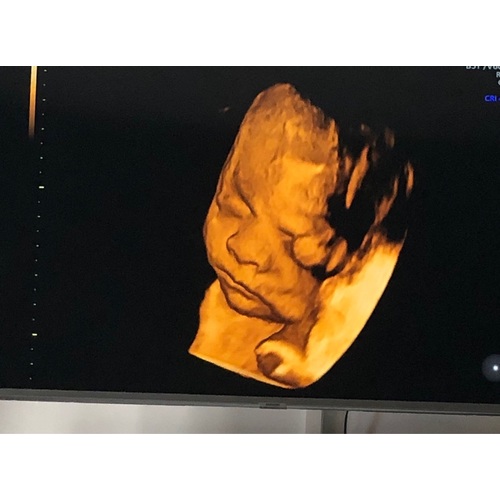

En deze nog met haar voetjes voor gezicht. Iets minder scherp maar vind het erg schattig 🥰